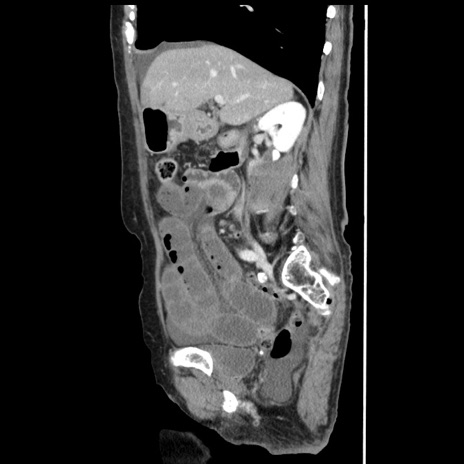

症例1(矢状断像)

【症例】80歳代女性

【主訴】腹痛

【現病歴】8時間前から腹痛あり来院。

【既往歴】糖尿病、脂質異常症、子宮体癌にて子宮全摘術

【身体所見】意識清明・会話良好だが腹痛で苦悶様、全腹部にわたって反跳痛と圧痛あり

【データ】WBC 13600、CRP 0.14、LDH 224、CK 90